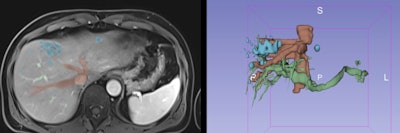

During the segmentation process, several techniques can be used to select the main structures, including thresholding, edge detection, region growing, and multiple-slice interpolation as well as manual segmentation with draw, paint, and erase/cut tools. 3D Slicer, an open-source software platform, was used for these models. All figures courtesy of RSNA 2020 and Nuno Pereira da Silva.

Liver metastasis of colorectal carcinoma. Five liver metastases were identified on MRI with hepatospecific agent. The 3D model was useful for surgical planning due to the well established relationships between the metastasis and the vessels as well as the 3D positioning of the nodules within the liver.

Liver metastasis of colorectal carcinoma. Five liver metastases were identified on MRI with hepatospecific agent. The 3D model was useful for surgical planning due to the well established relationships between the metastasis and the vessels as well as the 3D positioning of the nodules within the liver.3D models are increasingly used to help surgeons, guiding them through the complex hepatic vasculobiliary anatomy. They can help in the resection of hepatic primary tumors and metastasis because they can demonstrate the location within hepatic segments and the relationship with adjacent structures such as hepatic and portal veins, arteries, and bile ducts.